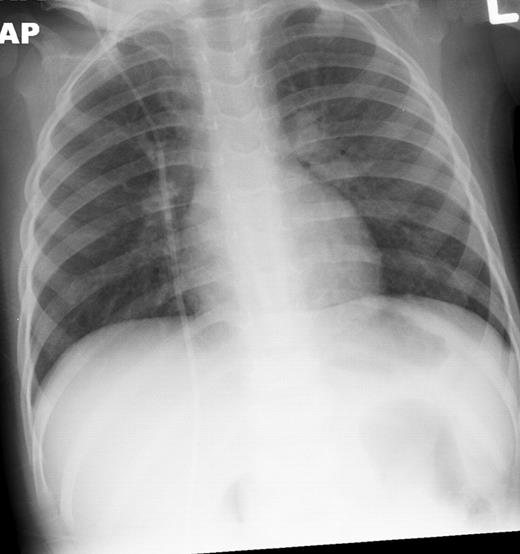

Our Patient, 8 weeks into chemotherapy for newly diagnosed ALL, presented with high grade fevers and poor activity. Patient was admitted 3 weeks prior for Bacillus cereus bacteremia. Additionally the patient had been on broad spectrum antibiotics on 2 occasions for febrile neutropenia episodes within the past 2 weeks. Patient had minimal respiratory symptoms at this presentation and recovered from pancytopenia at the time of this presentation. CT scans and chest x-ray (Figures 1 and 2) showed diffuse marked ground glass opacities with dependent consolidation in the lungs. On day 3 of admission, bronchoalveolar lavage (BAL) was preformed and empiric trimethoprim-sulfamethoxazole was initiated in addition to broad spectrum antibacterial, antifungal and antiviral medications.

Chest x-ray infiltrates